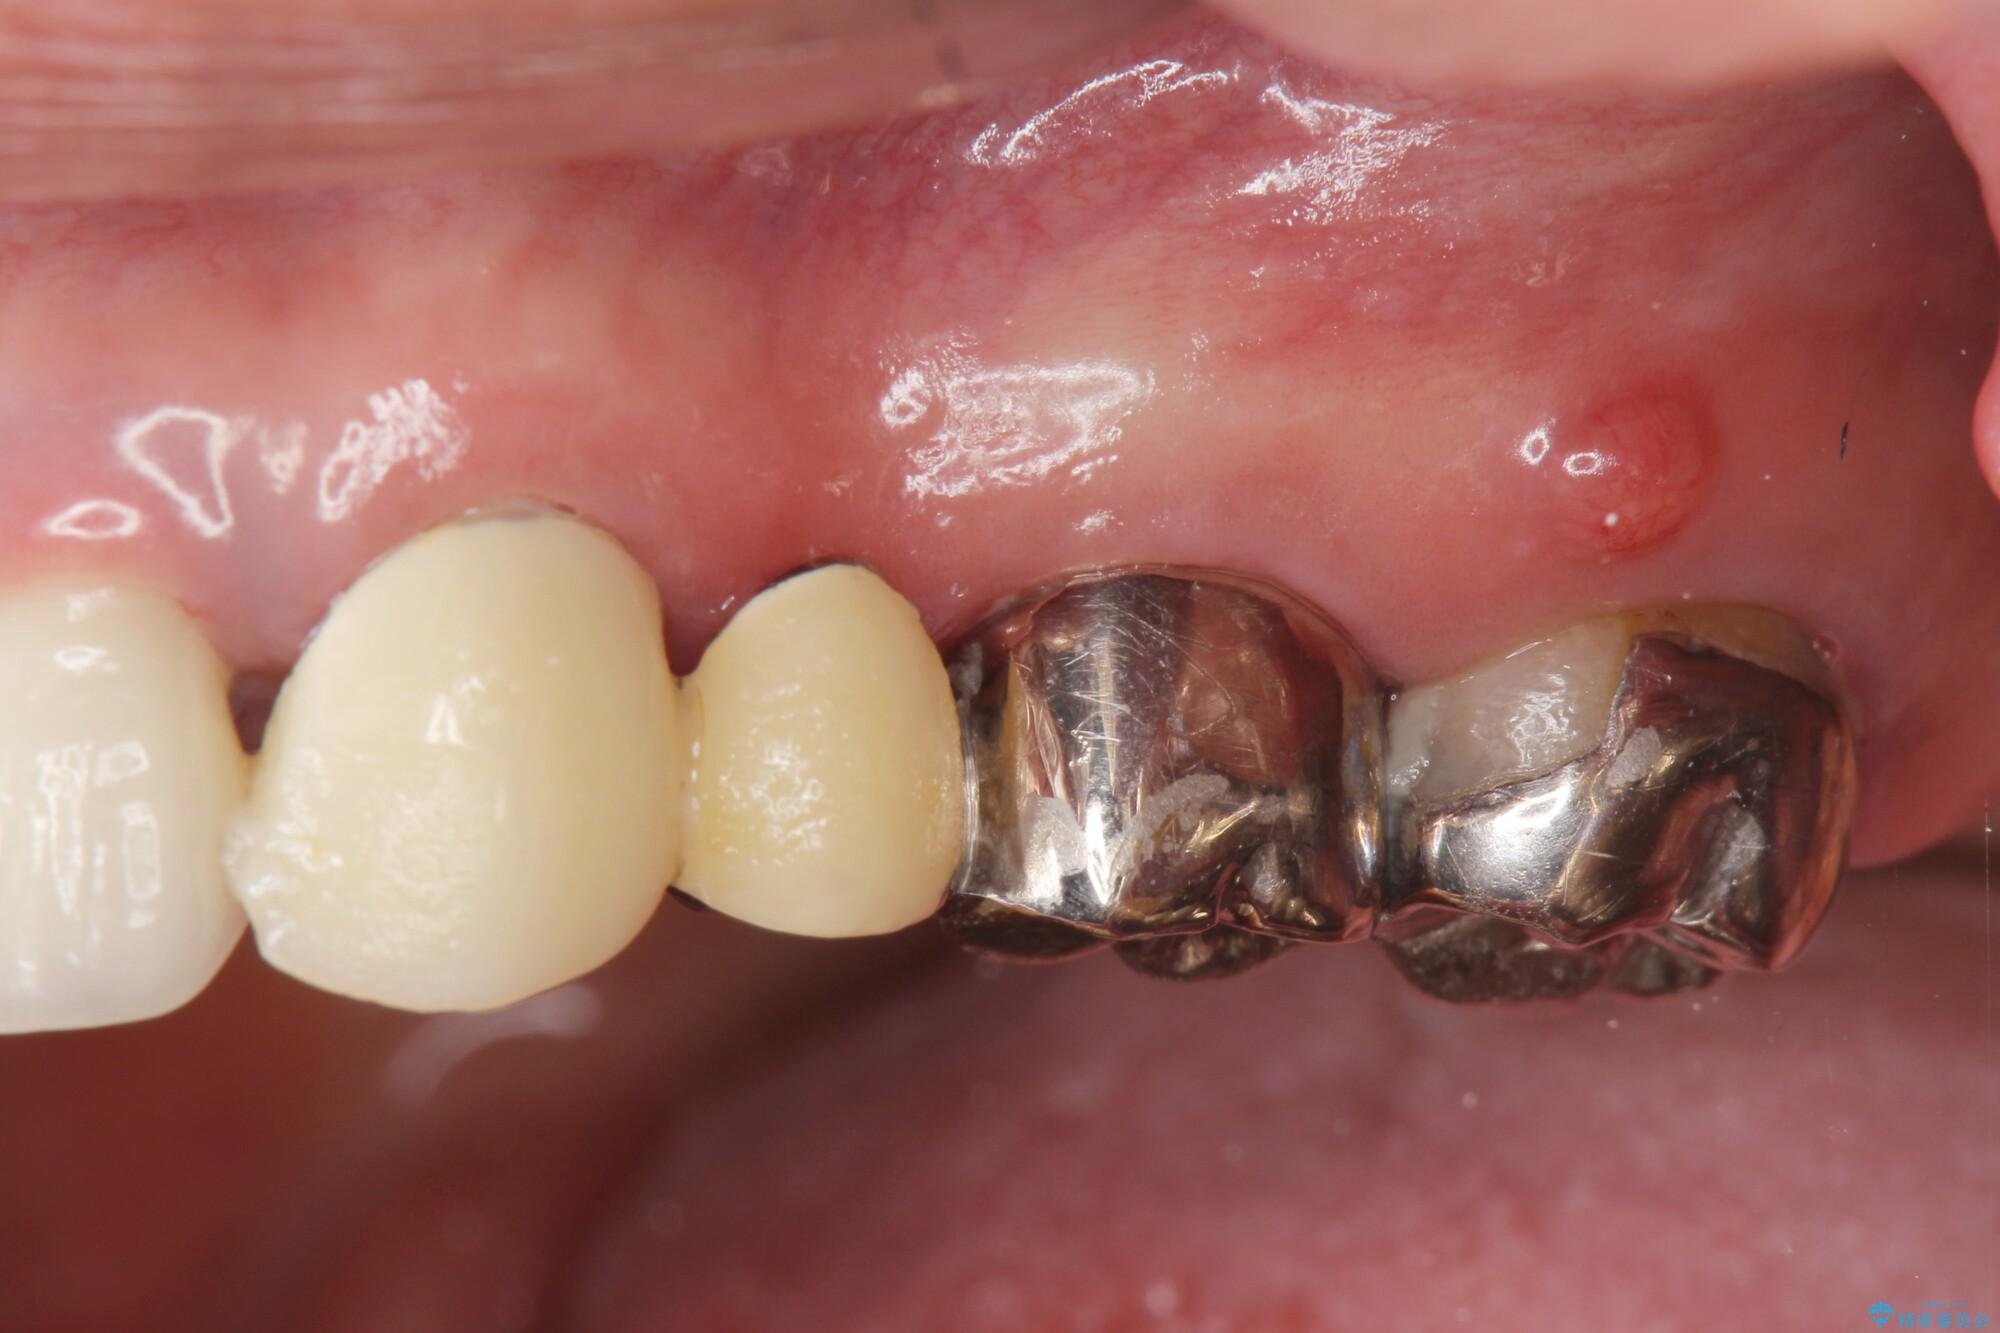

長い間気にしていた、笑ったときに見える銀歯を白くしたいとご来院されました。

まず検査を行い、歯周病や歯内の問題がないことを確認しました。

銀歯をジルコニアセラミックへと換えることで、審美性・清掃性の高い仕上がりを目指します。